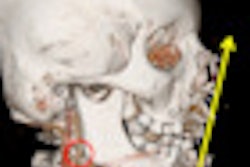

Patients with gunshot wounds are becoming increasingly common visitors in many emergency departments, especially those near large urban areas. These patients tend to have high mortality and morbidity rates, and injury assessment and evaluation of complications relies heavily on CT.

European Radiology has just published an important U.S. study involving 427 cases, and the article makes fascinating reading. The authors found that CT angiography can diagnose some unexpected injuries. To read more, visit our CT Digital Community, or click here.